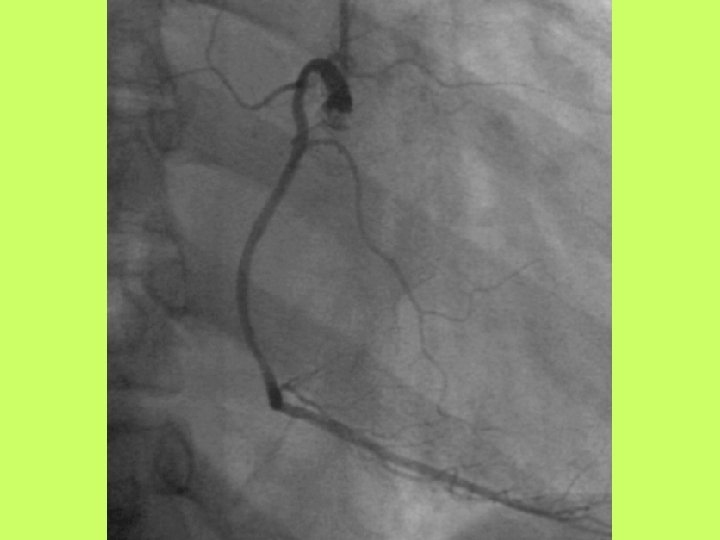

Noninvasive cardiac diagnostic studies 1 - EKG 2 -Chest X ray 3 -Exercise tolerance

Noninvasive cardiac diagnostic studies 1 - EKG 2 -Chest X ray 3 -Exercise tolerance test(ETT) 4 -Echocardiography transthoracic-trans esophagial 5 -Stress echocardiography 5 -Radionuclid imaging 6 -Cardiac catheterization